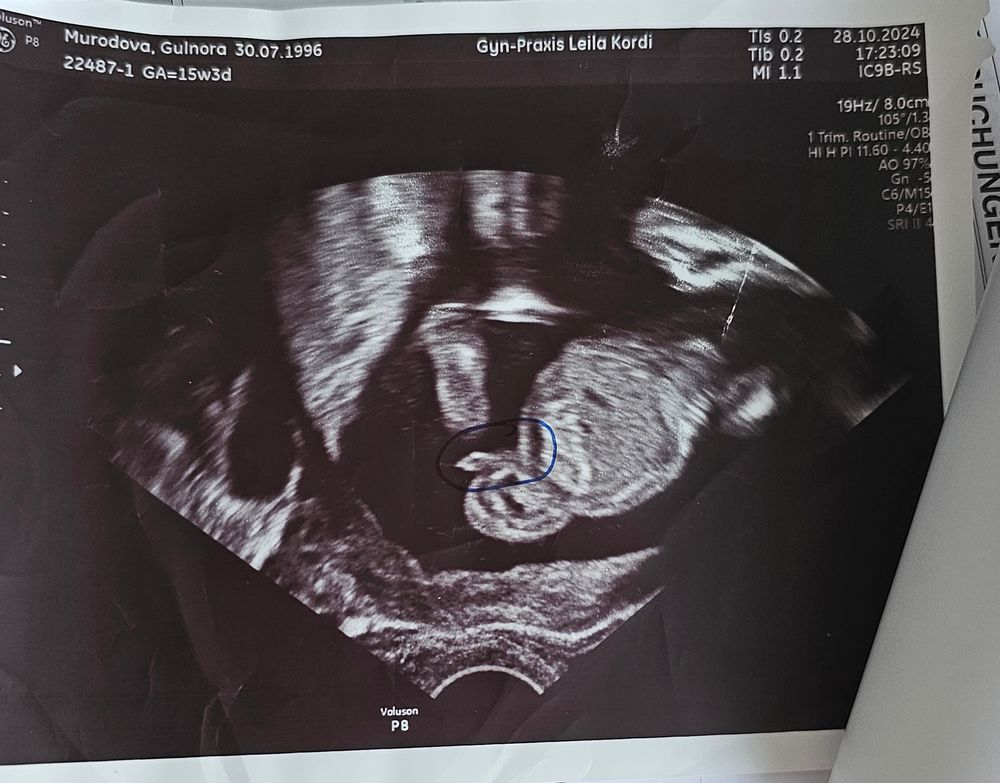

Беременность 22 недели мальчик

Беременность 22 недели мальчик 115 фото